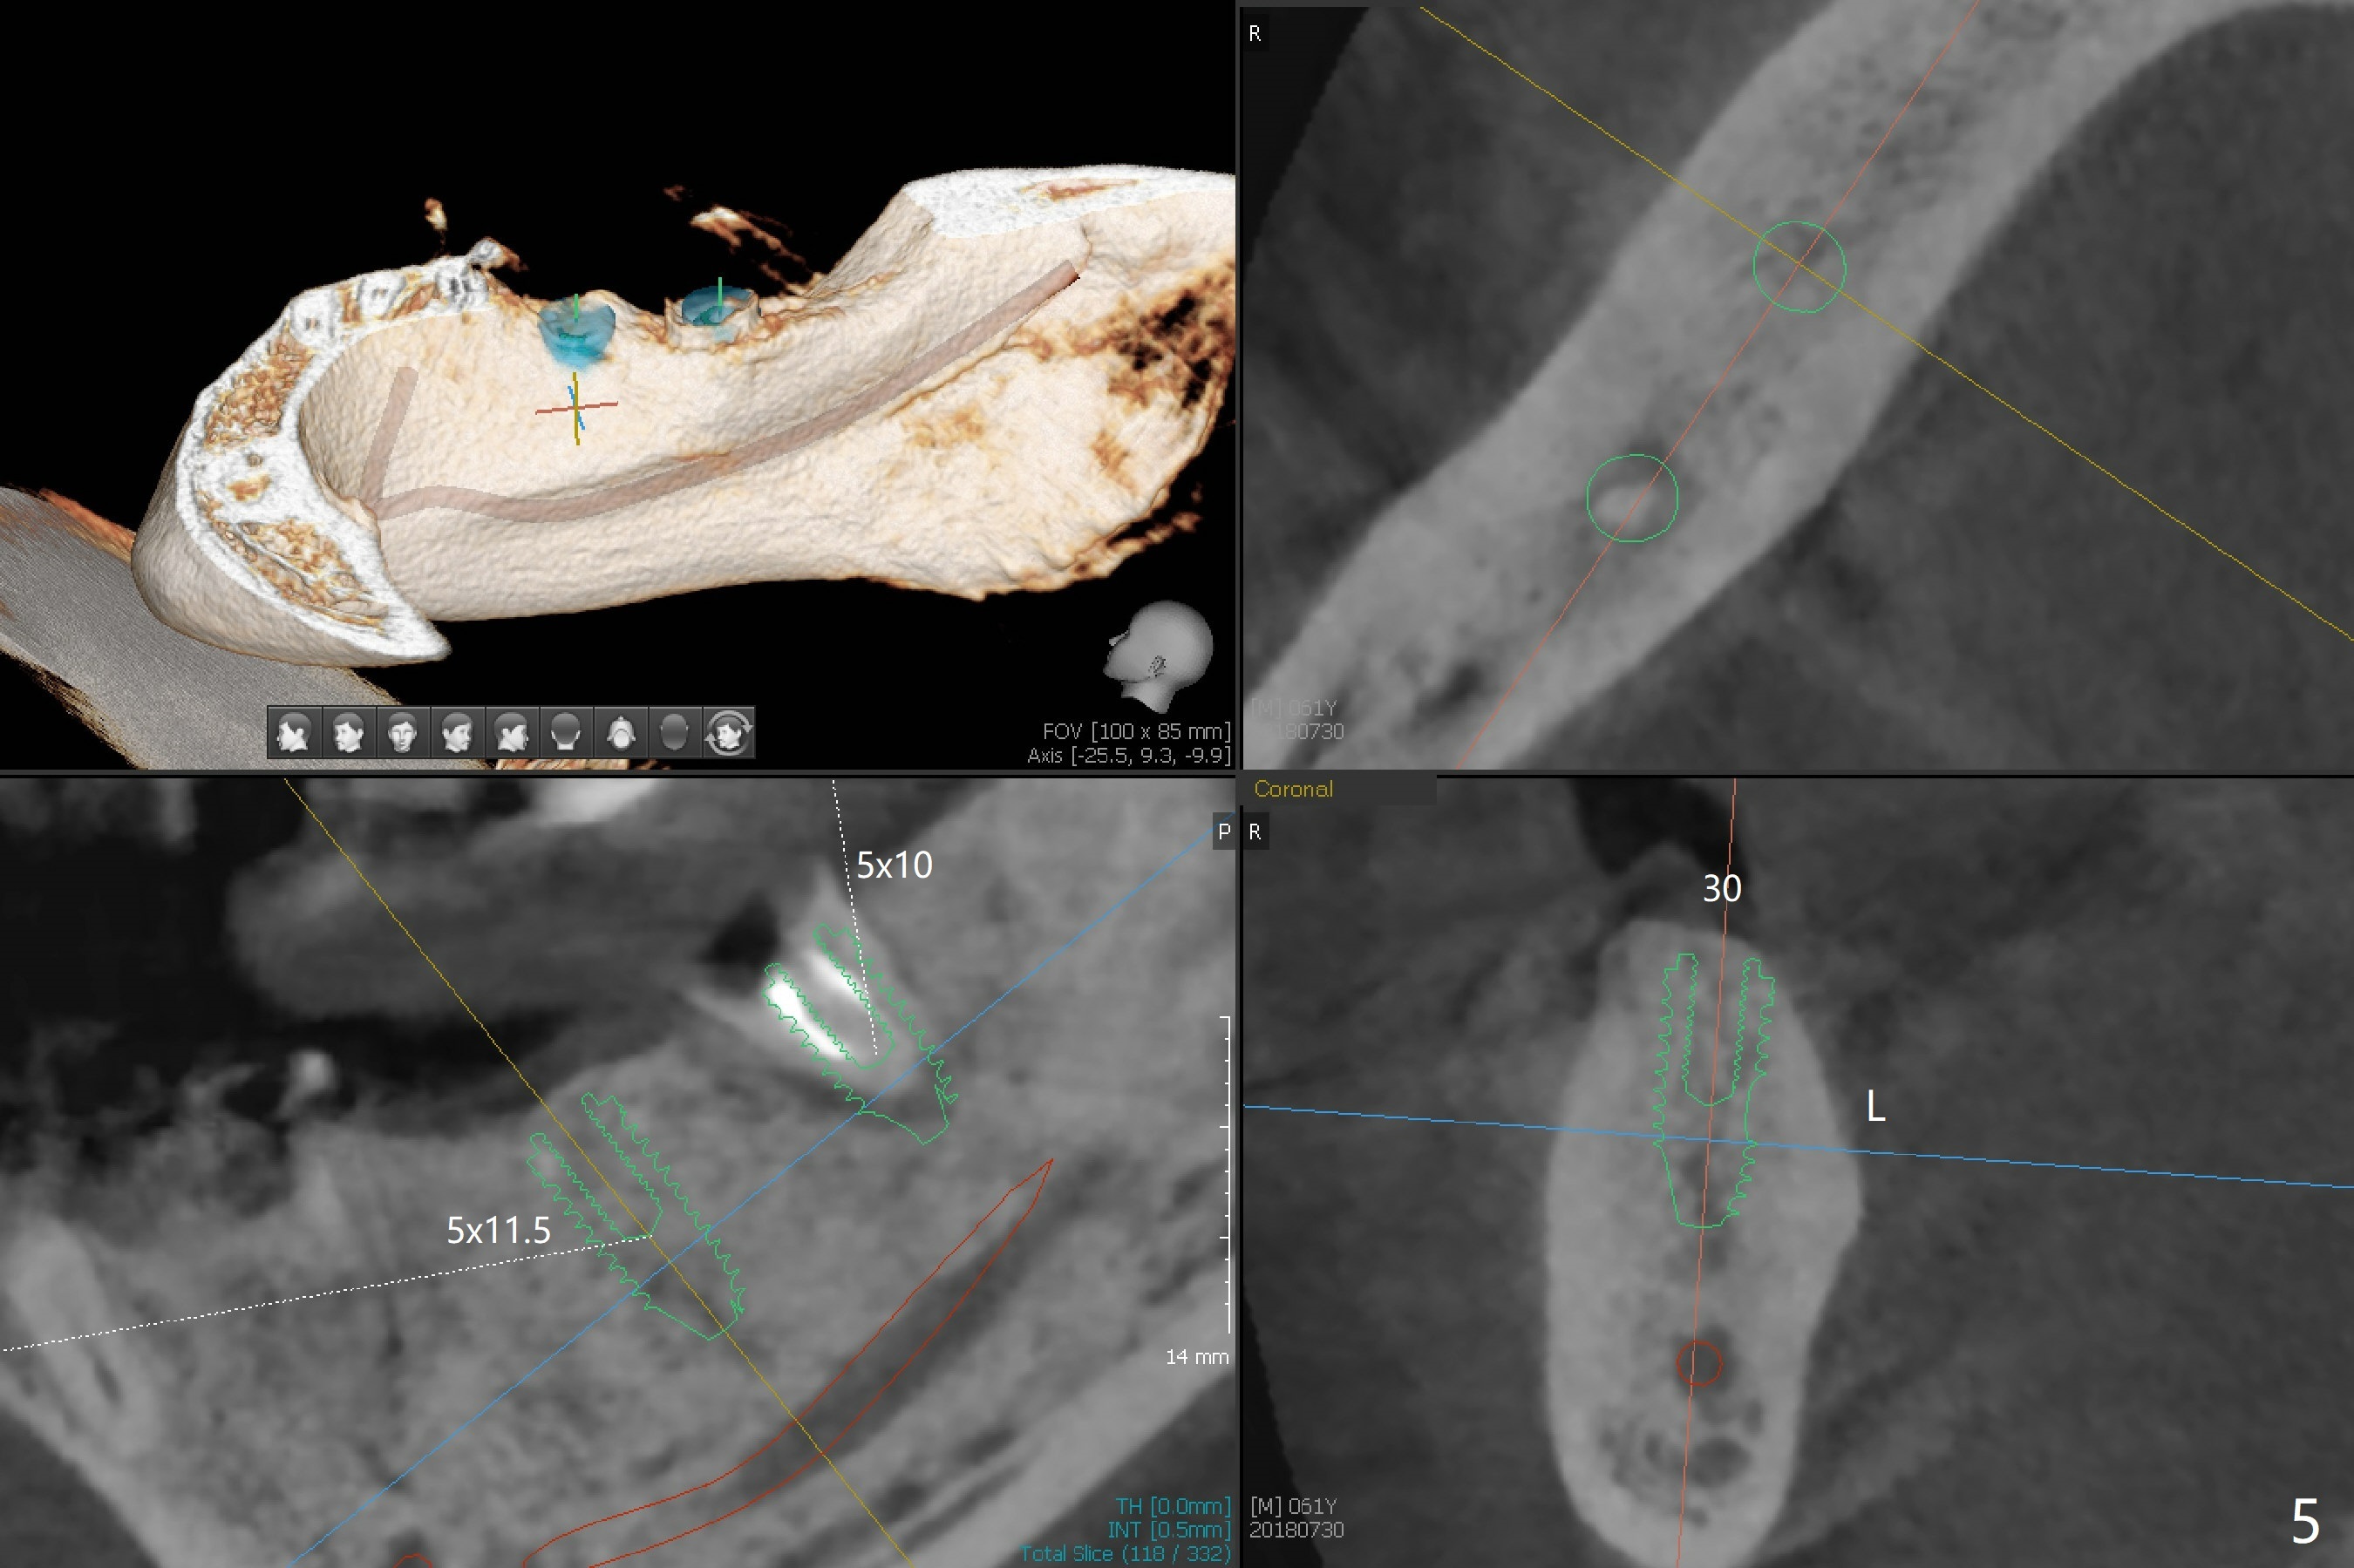

A 60-year-old man has lost a lower right FPD (Fig.1). The ridge at #30 is wide. To control implant spacing, PVS impression will be taken for guided surgery. Use the residual roots at #31 as a distal anchor tooth to finish implant placement at #30. After extraction, use implant anchor at #30 and finish implant placement at #31. Or 3-4 mm osteotomy will be initiated in the native bone using stopper for free hand (Fig.2 red line). An implant will be place ~ 1 mm subcrestal (green outline). Ask the lab to fabricate a stent for provisional with ~ 1 mm occlusal clearance.

My question is have you measured the how much remaining bones are left at the extraction socket. How much bone depth is left after the root extraction? Do you think the implant could get enough fixation after the extraction? Jennifer It is a good question. As today's CT indicates (07/30/2018), there is ~ 3 mm bone for primary stability with ~ 1 mm clearance (Fig.3-6). Because of the tapered implant, ~5 mm of the implant will be able to contact the native bone if the implant is lingually placed (Fig.6). If you feel it too much a risk, still make a guide for #31 so that an anchor pin can be placed at #31 residual roots for fixation (a new idea?). Make sure that the distal portion of the guide contacts the #31 residual root stump for stability, which is superior to a guide resting on the soft tissue. I have had experience placing implants free hand in this situation. The guide will be great help. I will use judgment in surgery. The worst scenario is socket preservation. Thanks for consideration and design.